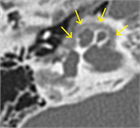

1. 前庭窓前縁の海綿状骨増殖によりアブミ骨固着が生じ、後天性・進行性伝音難聴を来す疾患である。両側罹患が多いが片側例もある。

1. 迷路骨包全体に脱灰病巣が拡大すると、蝸牛障害が加わって混合難聴、まれに高度難聴(中途失聴)に至る例もある。